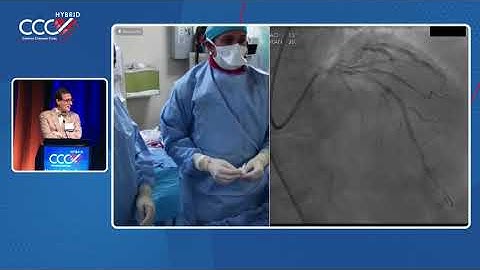

LIVE CASE 7 - PCI of LAD CTO with Antegrade Wiring Technique